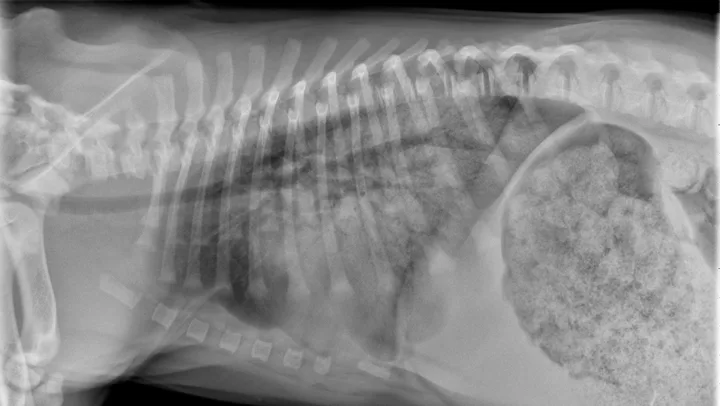

Dogs with bacterial pneumonia are typically presented with acute-onset coughing, lethargy, inappetence, and/or respiratory distress. An inflammatory leukogram and pyrexia, although common, are not always present. Radiographs may reveal an interstitial-to-alveolar pattern with a cranioventral distribution (Figure 1). Atypical distributions can also occur.5

FIGURE 1

(A) Bronchopneumonia. Cranioventral distribution of alveolar disease with air bronchograms. (B) A patchy distribution can be observed on the lateral projection. The changes overlying the heart may be missed in subtle cases.